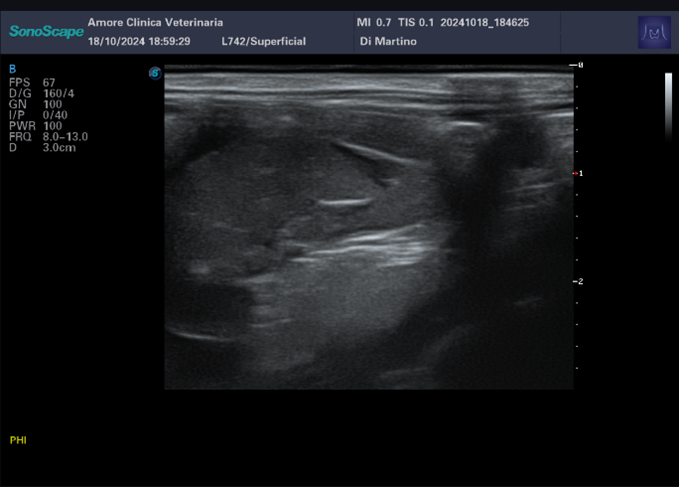

l’esame ecografico addominale rileva un dislocamento dell’apice del lobo epatico destro con presenza di una discreta falda di versamento ipoecogeno particolato.

Effettuata la centesi, il versamento risulta essere di tipo emorragico.